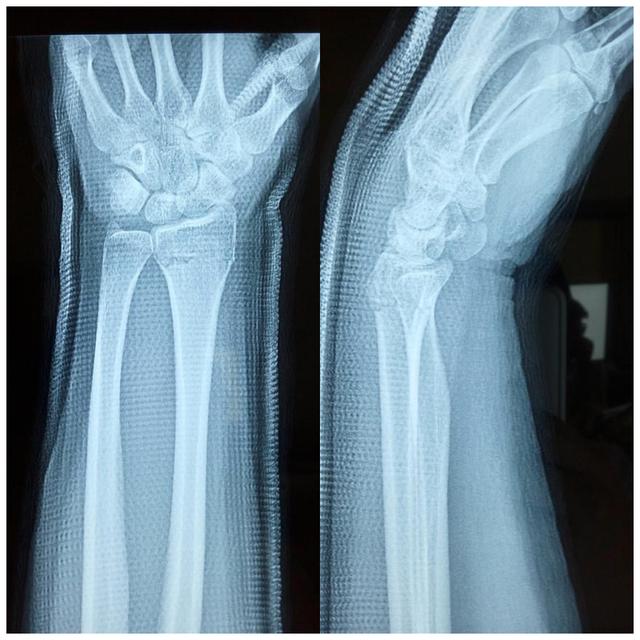

桡骨

桡骨远端骨折分型,桡骨远端骨折有哪些分型(桡骨远端骨折的AO分型)

手术前X片